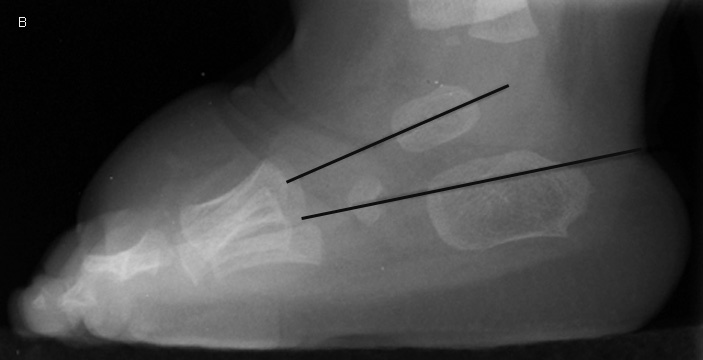

Club Foot (talipes equinovarus)

M>F, 50% bilateral

4 components: hindfoot varus, calcaneus equinus *(en pointe), metatarsus adductus, and talonavicular subluxation

Rocker Bottom Foot

A/w TS18, TS13, 18 Deletion, spina bifida, arthrogriposis

components: fixed equinus (rigid flat foot)

vertical talus *they both look en pointe

forefoot valgus